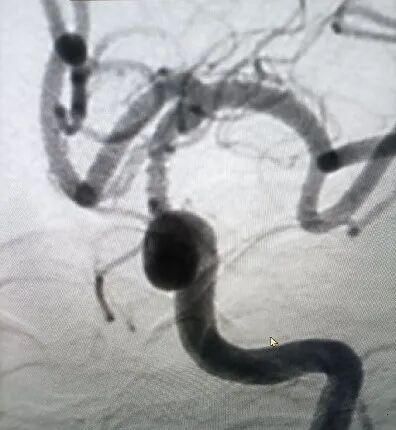

球囊通过病变扩张血管后,残余狭窄30%,局部血管夹层可疑。远端通路导管在球囊导管的引导下通过迂曲的C3、C4段,抵达病变血管近端。

导丝怎么扩【载药时代 球扩天下】NOVA DES®颅内药物洗脱支架在颈内动脉颅内段重度狭窄的应用两例!滕州市中心医院&山西医科大学第二医院_https://www.jmylbn.com_新闻资讯_第18张

中间导管到达病变处。

赛诺神畅 NOVA DES®内药物洗脱支架2.5*12mm到位。

释放后造影。